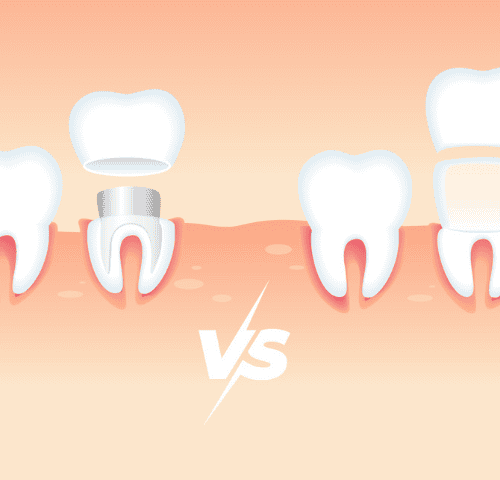

Veneers vs. Crowns: A Guide to Choosing the Best Option in Turkey

Veneers vs. Crowns: A Guide to Choosing the Best Option in Turkey is an article that aims to give you all the information you do not know about Veneers vs. Crowns: A Guide to Choosing the Best Option in Turkey and more.

Dental Crowns in Turkey

Dental Crowns in Turkey is an article that aims to give you all the information you do not know about Dental Crowns in Turkey and more.

Dental Implants in Turkey: Types, Prices, Procedures

Dental Implants in Turkey: Types, Prices, Procedures is an article that aims to give you all the information you do not know about Dental Implants in Turkey and more.